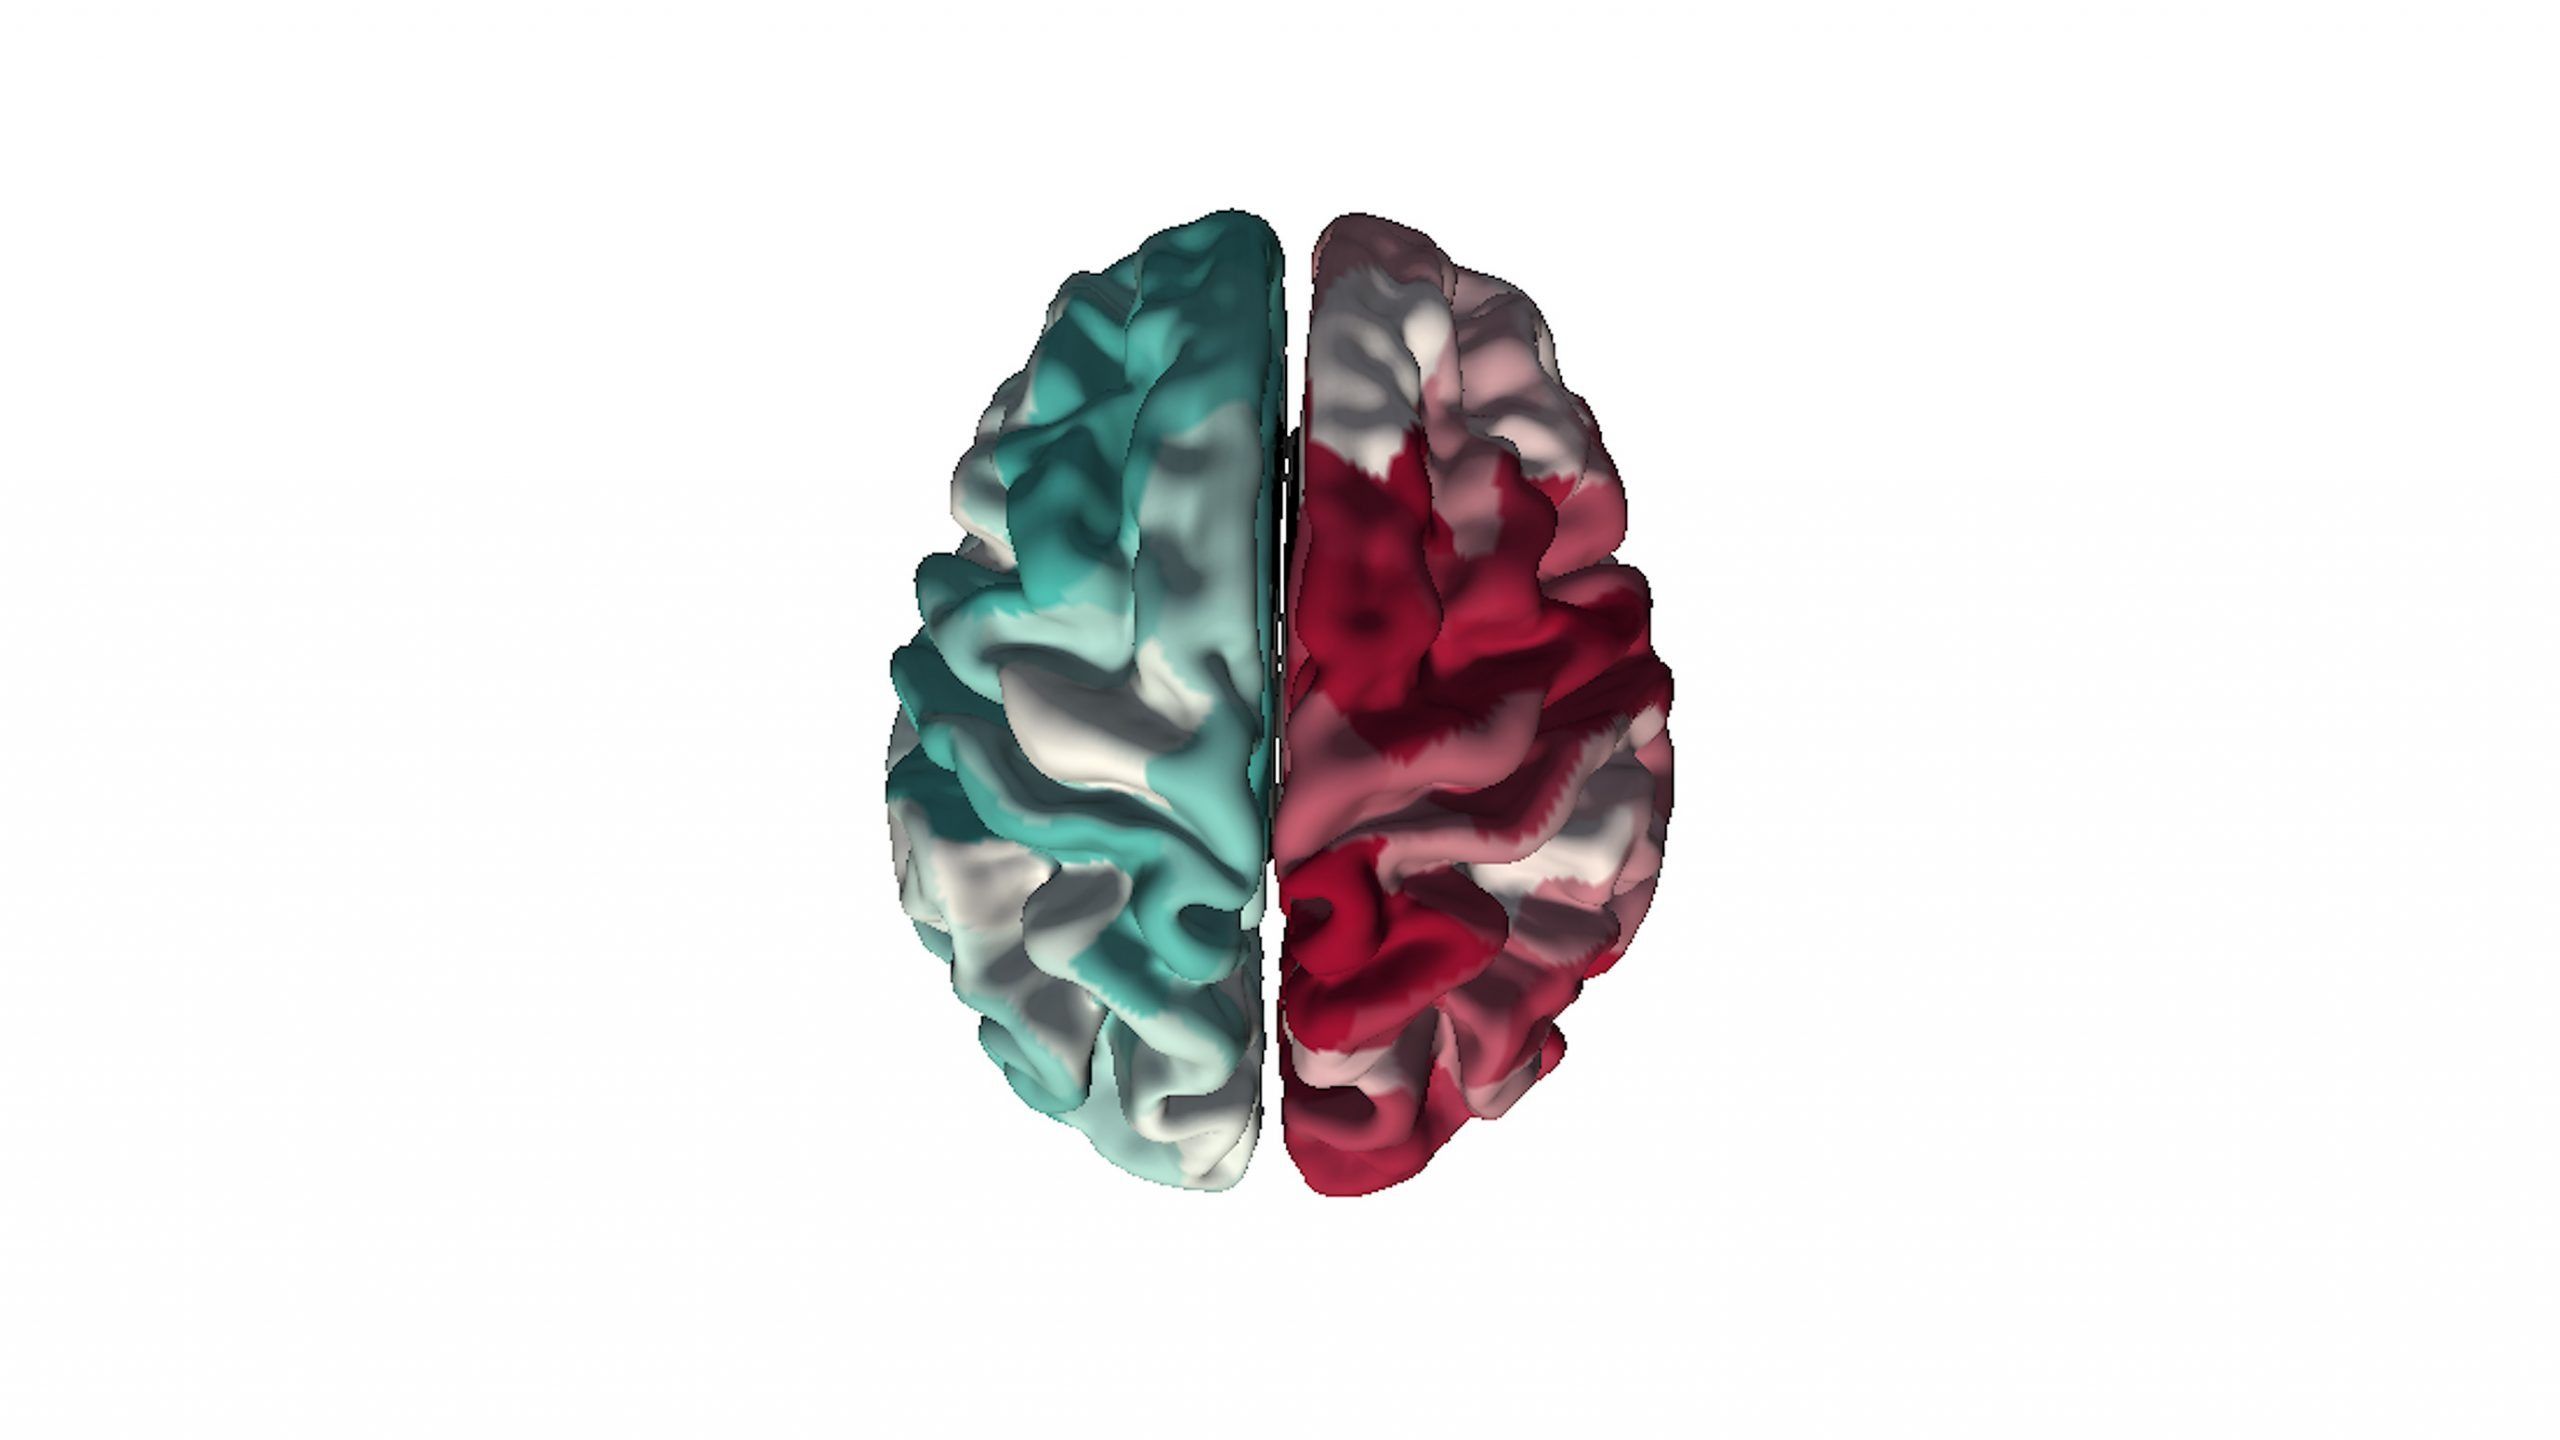

When examining athletes experiencing severe post-concussive symptoms, Monroe and his team found differences in the shapes of some parts of the brain. The structural changes the team found, seen below on the left, correlate with a pattern of “risky” gene expression previously identified in post-mortem studies of brains, which is visualized on the right.